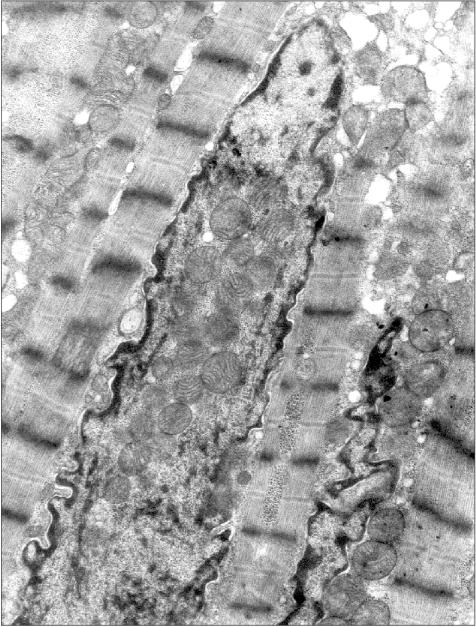

Figure 1 presents three patients' cardiomyocyte nuclei that contain mitochondrial clusters. Two patients were with hypertrophic cardiomyopathy and the third patient had alcoholic cardiomyopathy. One can see that the mitochondria are not separated by the nuclear membrane from the nuclear contents. This means that mitochondria are present in the nucleoplasm and not in a nuclear envelop invagination. All three microphotographs show the continuity of the nuclear membrane that separates the nuclear interior (with the mitochondria) from the cytosol.

Figure 1c

Fig. 1c. Intranuclear location of mitochondria in cardiomyocytes of patients with heart failure: patient Kh. (alcoholic cardiomyopathy); ×73,400.

Examination of microphotographs of the mitochondria-containing nuclei shows that in most cases we are dealing with the cells that are entering apoptosis. Thus, most of the figures in the present article show chromatin margination (the accumulation at the edges of the nucleus) that is typical for apoptosis.